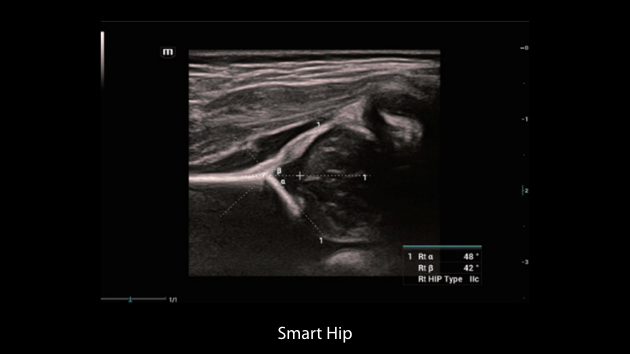

Nuewa I9 Elite Edition ├© progettato appositamente per l'assistenza sanitaria a donne e neonati e offre un'esperienza innovativa sviluppata sulla base di conoscenze approfondite relative a scenari clinici complessi, per risposte accurate e tempestive, nonch├® un'efficienza e un'esperienza utente eccezionali